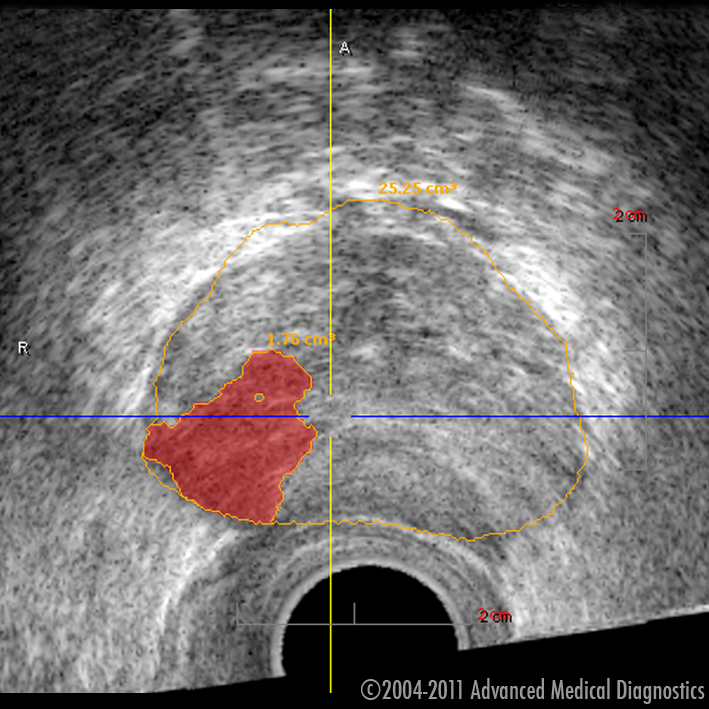

Ar 3D histoskeneri var „ieraudzīt” prostatas vēzi

Sagaidot 4. februāri – Pasaules Pretvēža dienu –, Rīgas 1. slimnīcas telpās tika prezentēta inovatīva trīs dimensiju histoskenēšanas tehnoloģija, kas Latvijā tiek izmantota pirmo reizi. Jaunā aparatūra izmeklējuma laikā urologam ļauj novērtēt prostatas stāvokli, precīzi nosakot no normāliem audiem atšķirīgu audu atrašanās vietu, kas liecina par vēzi.